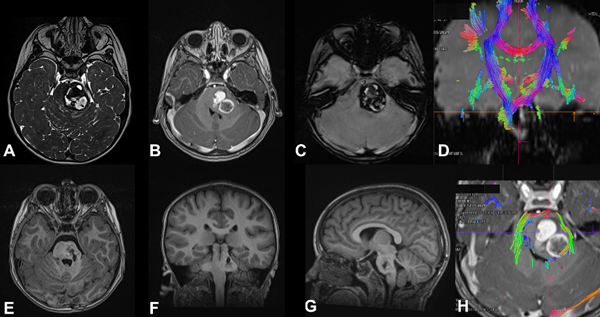

Figura 3. MC cerebral infratentorial del tronco del encéfalo. Paciente masculino de 5 años que ingresa por síndrome cerebeloso, asociado a hemiparesia faciobraquiocrural izquierda. Evoluciona favorablemente, egreso hospitalario. A los 2 meses reingresa por un episodio de resangrado. Se decide cirugía programada. A) RM T2 FIESTA que muestra lesión protuberancial, heterogénea, con halo hipointenso. B) RM T1 con contraste EV que muestra sangrado en distintos estadios. C) RM SWI imagen típica. D) y H) RM DTI-tractografía que muestra tractos pontinos transversos en rojo y pedúnculo cerebeloso medio en verde, en este caso se eligió un abordaje supracerebeloso infratentorial lateral y se accedió al cavernoma a través del surco mesencefálico lateral. E-G) RM postquirúrgica de cerebro secuencia T1 en los 3 planos, se evidencia la resección completa de la lesión.

De acuerdo con la bibliografía, entre el 10 y el 23% de las MC se encuentra a nivel de la fosa posterior, predominantemente en la región de la protuberancia, pudiendo encontrarse en hemisferios cerebelosos o en el resto del tronco del encéfalo. En nuestra serie obtuvimos resultados similares, con 30% de las lesiones de ubicación infratentorial, siendo dos tercios de ellas a nivel del tronco cerebral (ver Figuras 3 y 4).3,5,18,24,25,34

Dos de los tres casos que presentamos requirieron tratamiento quirúrgico (ver Figuras 3 a 5) debido al déficit neurológico progresivo que interfería con la calidad de vida y al efecto de masa con desplazamiento de las estructuras bulboprotuberanciales circundantes. Ambos casos presentaron mejoría sintomática postquirúrgica, con recuperación parcial del foco neurológico, sin nuevos déficits asociados al procedimiento.